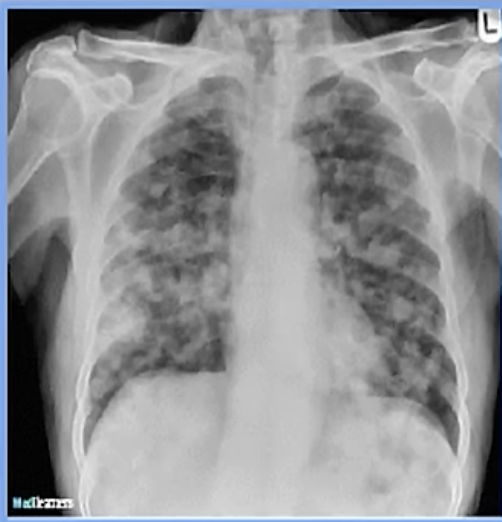

Imagen de una neumonia viral

20